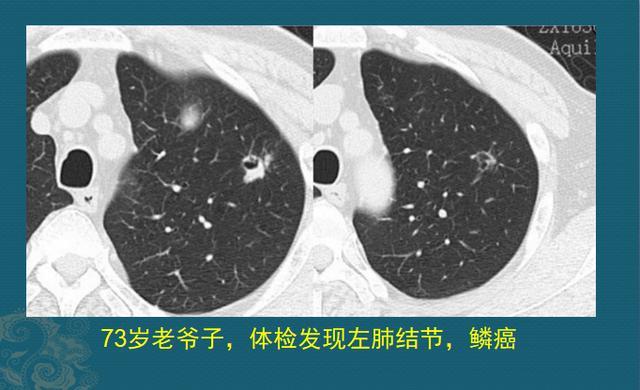

病例1,坏蛋很小,一锅端

都说“73、84,阎王不叫自己去”,但有时候孝心可以续命延寿。下面这位73岁老爷子,有点小咳嗽,孩子们逼着做体检,结果发现左侧肺鳞癌,已经手术切除好几年了:

图片